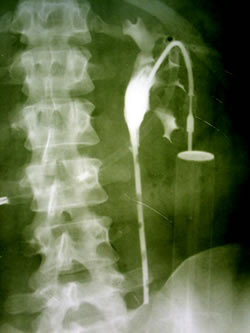

|

Экскреторная

урография |

Ретроградная

уретеропиелография |

КТ-урография:

чашки левой почки 1,5см, лоханка 2,8см, в в/з

и лоханке имеется объемное образование размерами

2,5см х 2,0см на широком основании. Забрюшинные

лимфатические узлы не увеличены